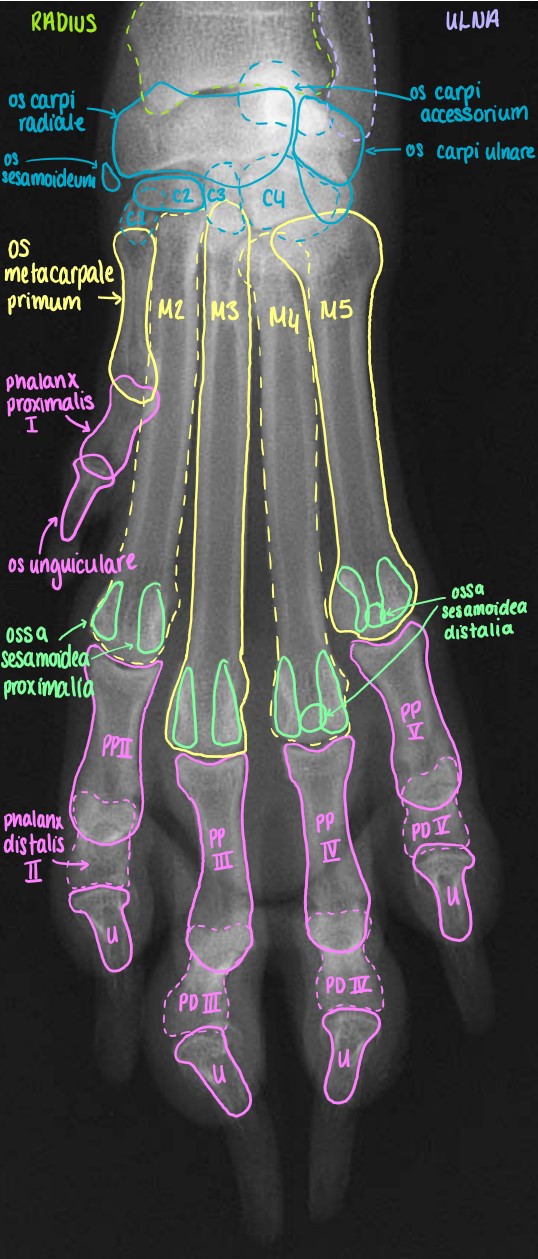

Manus